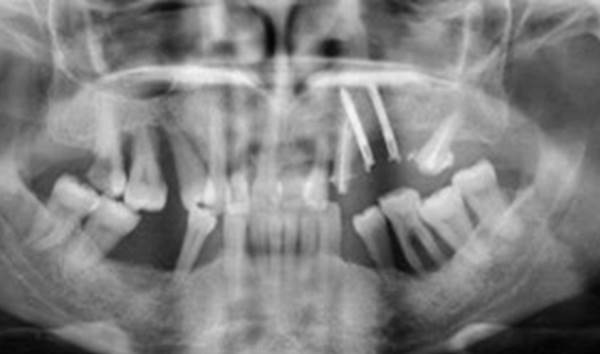

Clinical case: Full-mouth implants for mandibular & maxilla - restored using mixed prostheses

- Courtesy of Dr. Hyun Jun Kim, Korea -

“AnyRidge ensures long-term biological stability

& functionality even in

full-mouth rehabilitation case. ”